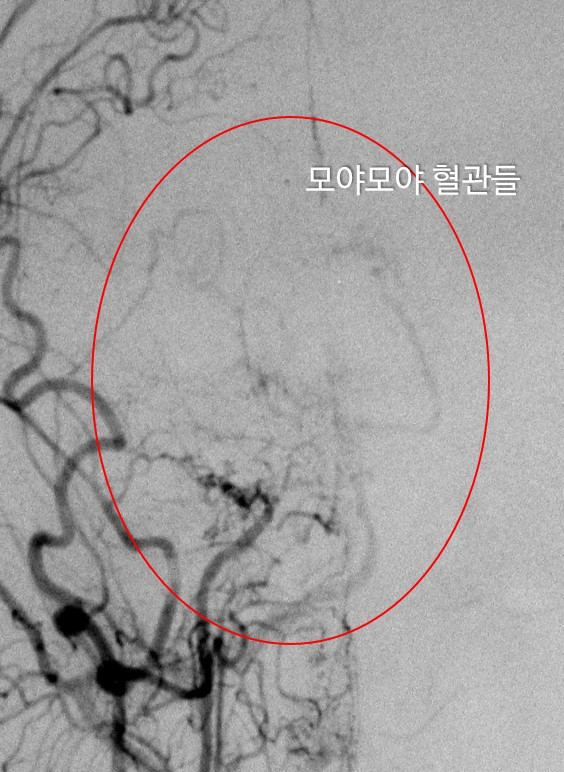

모야모야병은 일본어인 もやもや 에서 유래되었다. 모야모야는 연기가 피어오르는 모양을 나타내는 일본어인데, 실제 모야모야 병에서 뇌혈관의 모양은 마치 연기가 피어오르는 것처럼 보인다.

위에 우측 사진에서 보이는 것처럼 뇌혈관의 모양은 양갈래를 뻗은 나무줄기처럼 생겼다. 하지만 모야모야 병 환자의 경우 좌측의 사진과 같이 뇌혈관이 굵은 줄기가 없이 무수히 많은 잔가지만을 낸 것처럼 보인다. 이러한 병적인 혈관들을 모야모야 혈관이라고 부른다. 당연하지만 이러한 모야모야 혈관들은 정상 혈관에 비하여 매우 약하다.